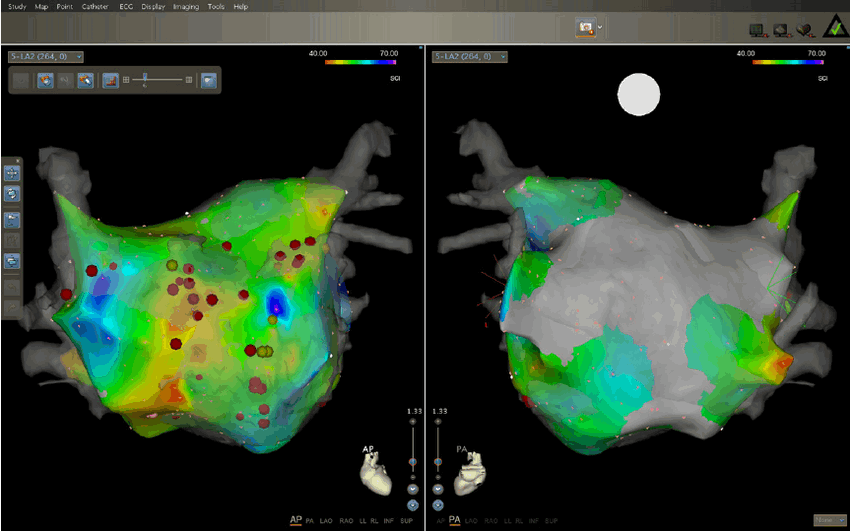

Estudo

Eletrofisiológico

Durante o procedimento é possível analisar os intervalos de tempo que o sistema de condução necessita para permitir a passagem do impulso elétrico, bem como estimular o coração para pesquisar a presença de determinados tipos de arritmias.